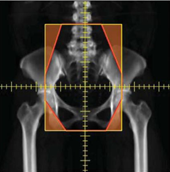

基于骨骼标志的4场盒处理(包括梁重优化)

ctv和正常组织的轮廓

4场盒处理基于CTV轮廓